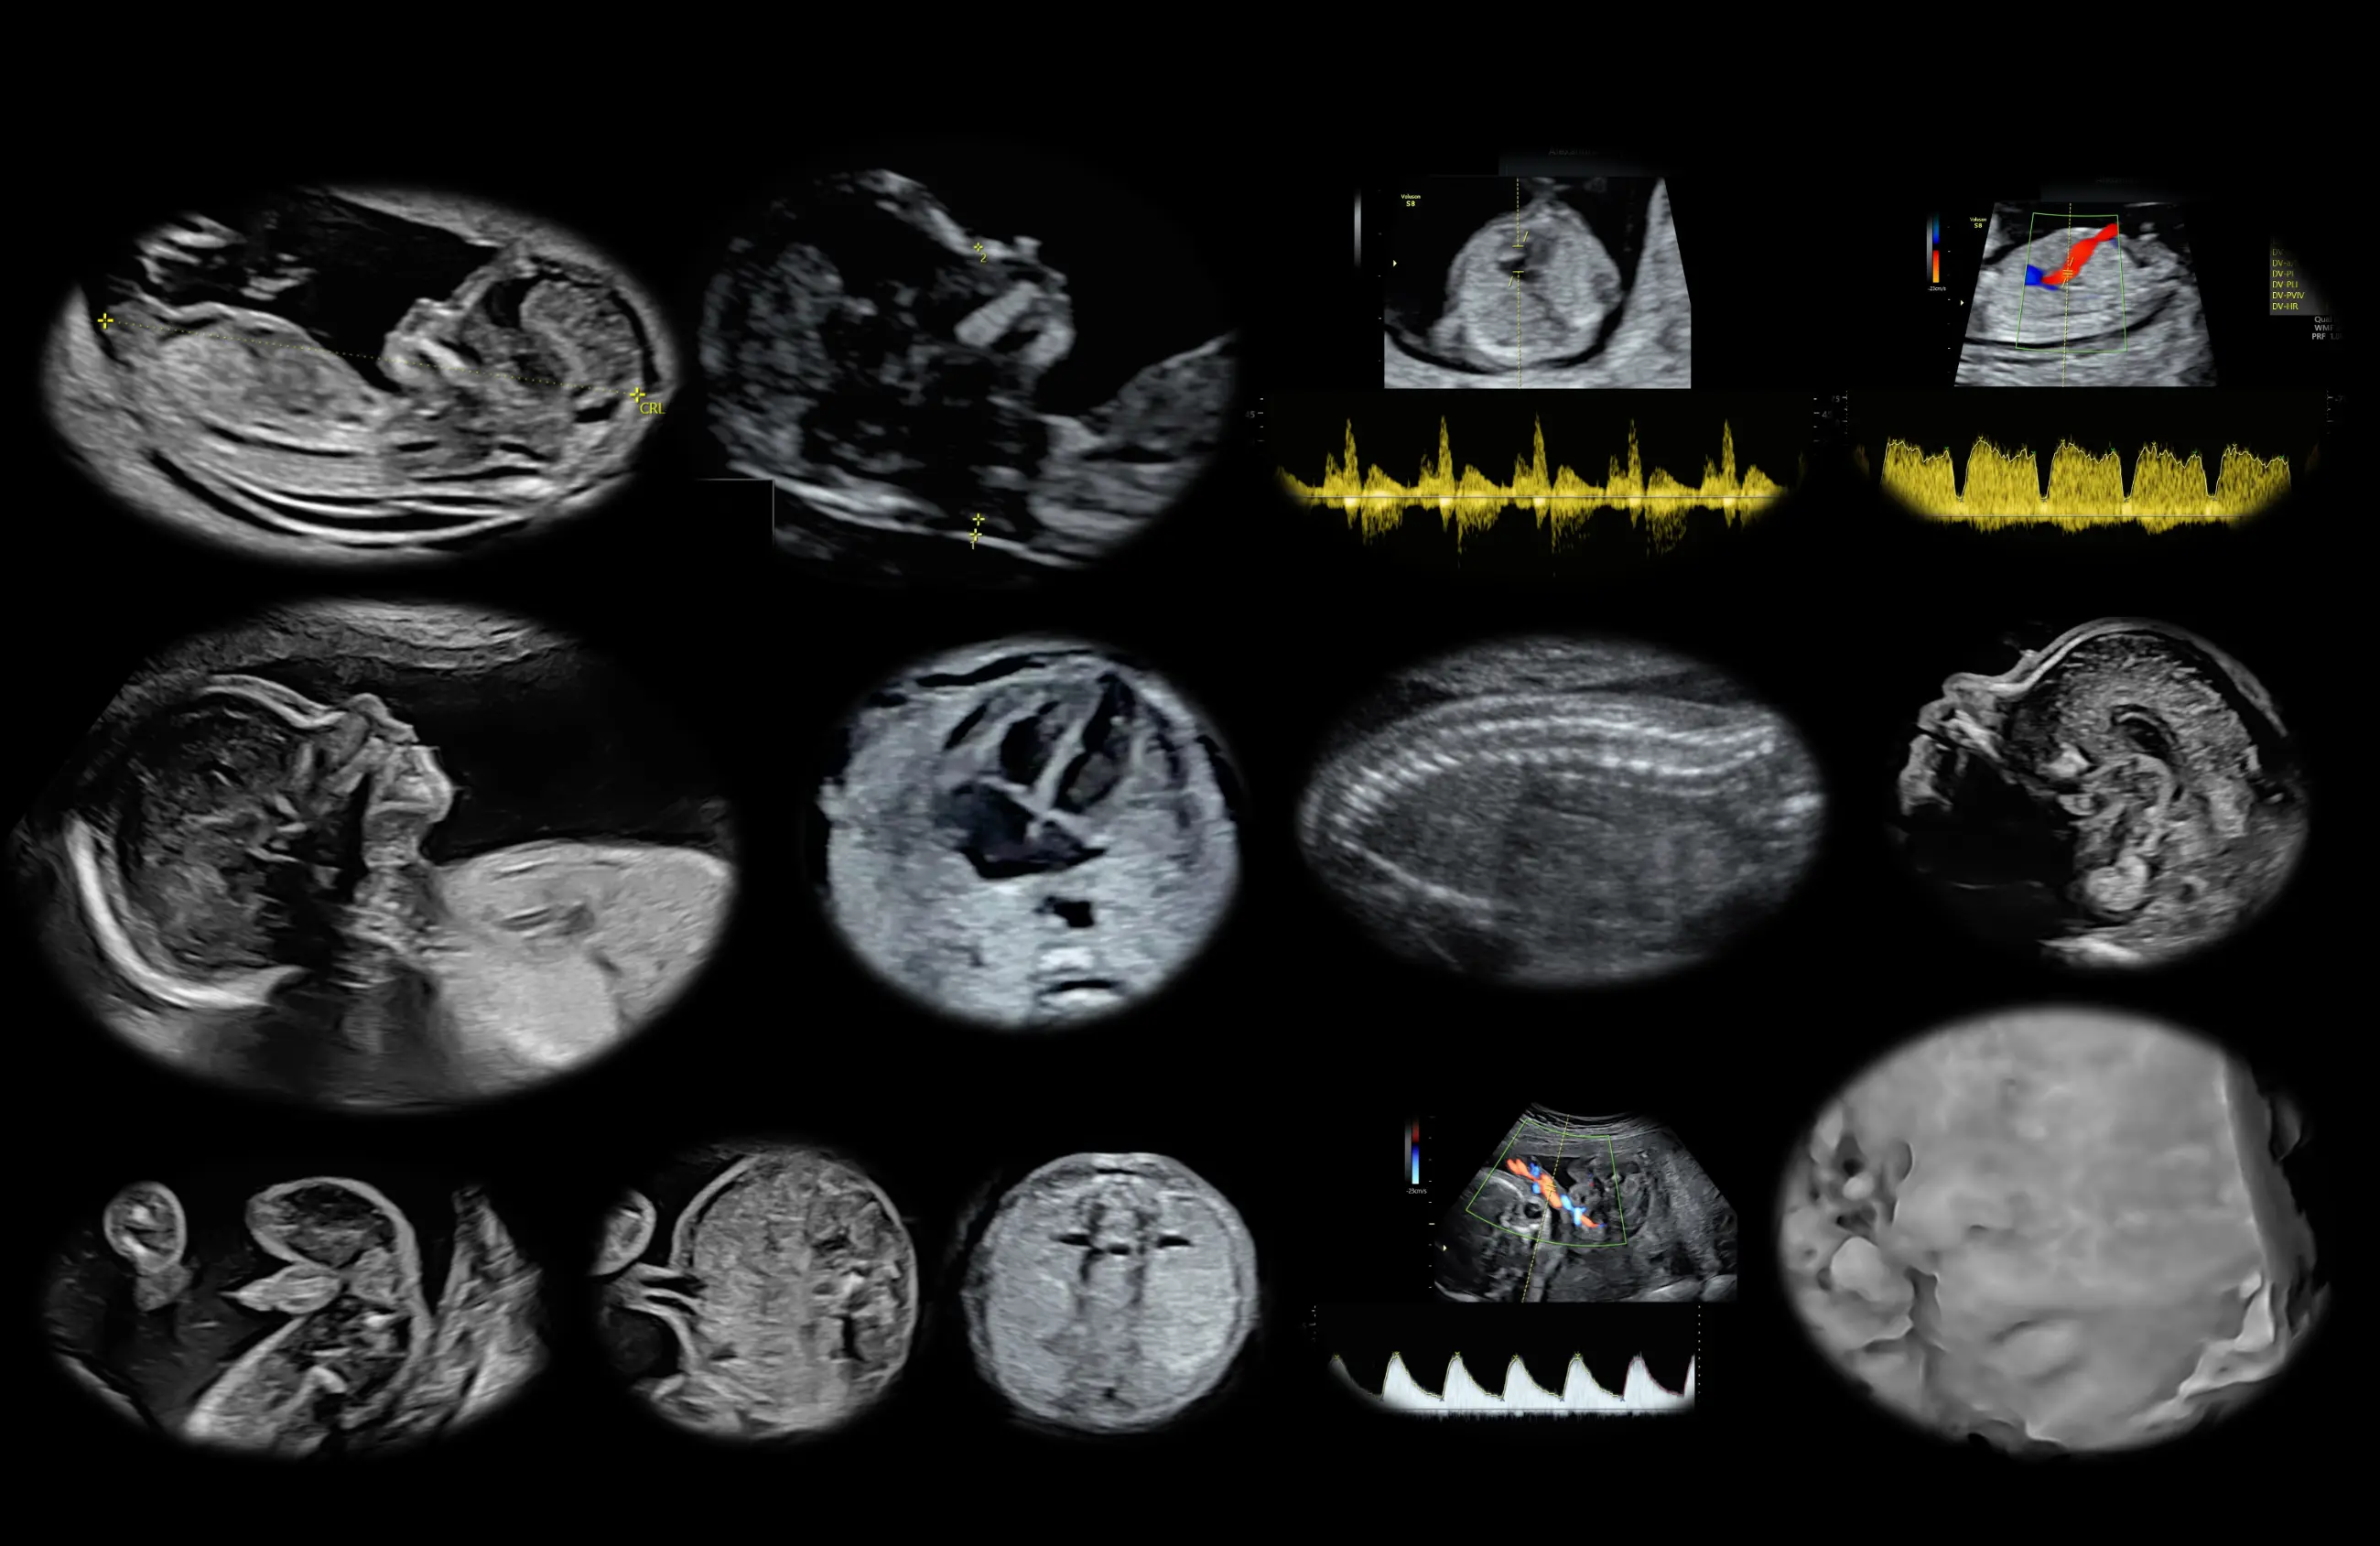

Image

Υπερηχογραφήματα